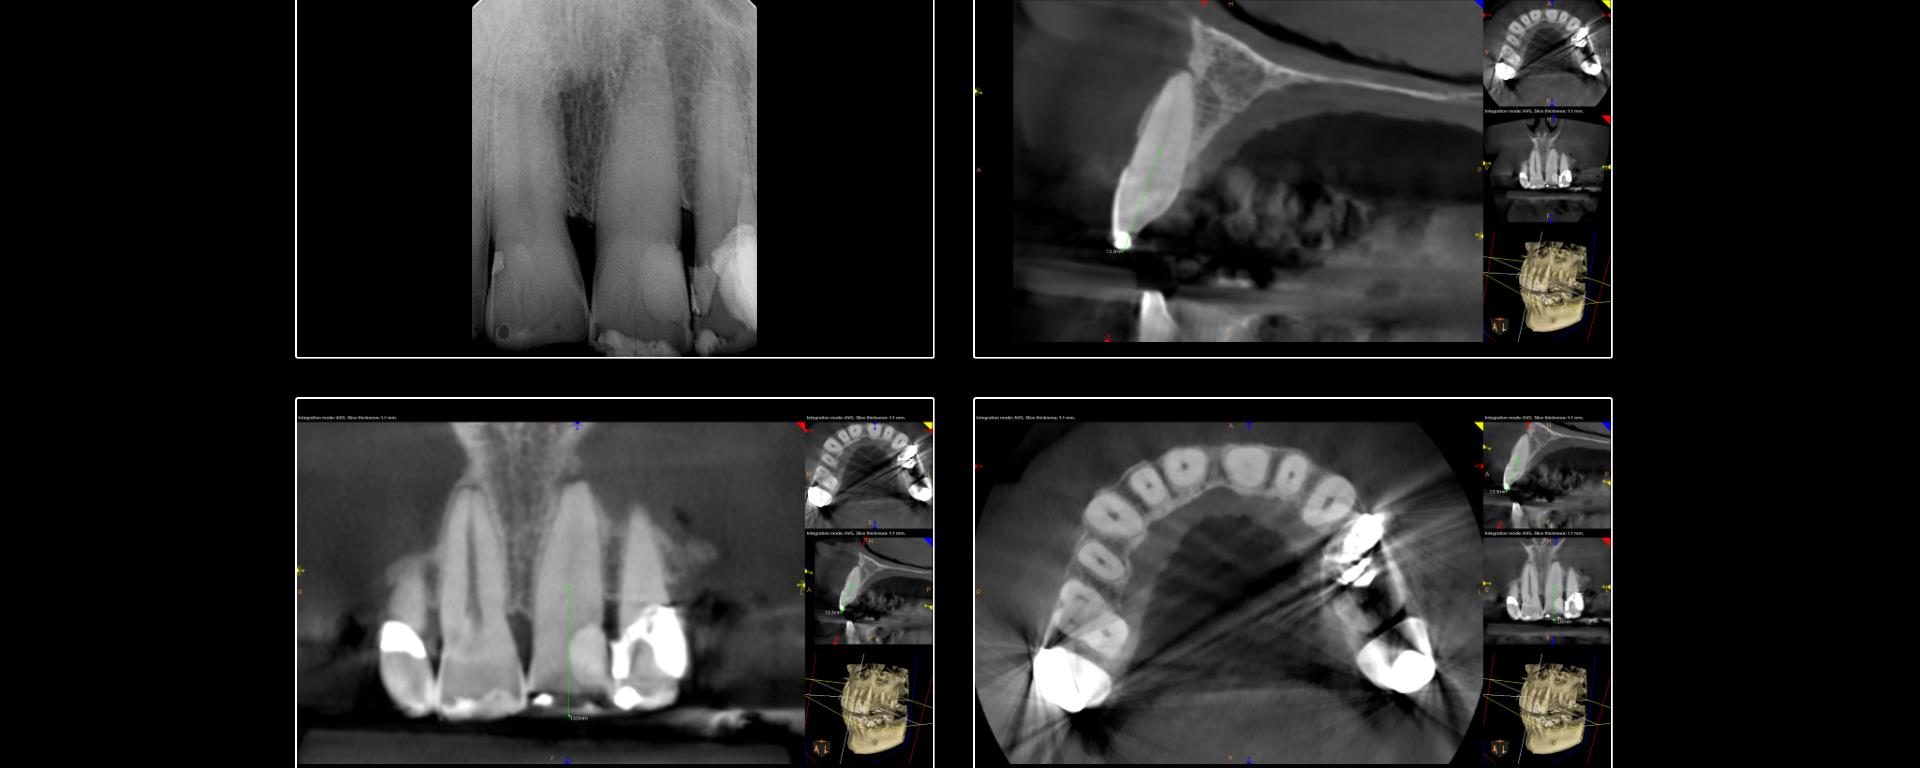

This case was started in February and completed on Monday. We are currently bleaching the tooth. The buccal plate has regenerated rather nicely and the finding is continuing to heal. -Charles